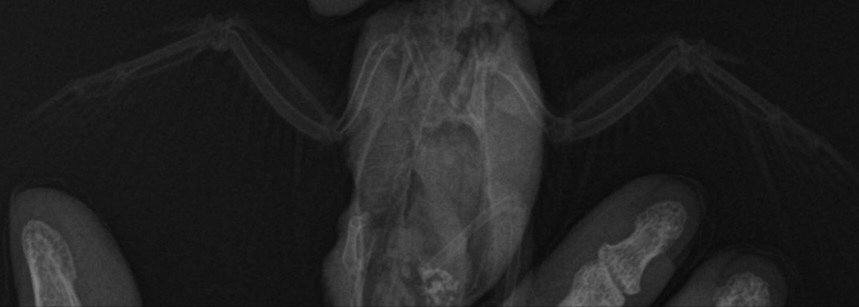

Вывих крыла и неоплазия

Помогите пожалуйста разобраться, птицу купили 2 недели назад, писала тут, что он не может летать, поняли это когда впервые попробовали выпустить. Сегодня дождались записи ветеринара, он посмотрел птицу, сделал снимок, сказал, что это вывих. Описание снимка сказали подождать, будет после того, как специалист из другого города опишет. В итоге вечером мне прислали описание снимка, прилагаю текст и теперь я совсем не понимаю. Там и травма и но образование. В ветеринарной клинике, где мы были молчат, больше никаких консультаций не дали мне. Можно ли что-то понять по приложенному сниму и описанию? Я верно понимаю, что дело не только в вывихе, а по снимку обнаружена какая-то опухоль?